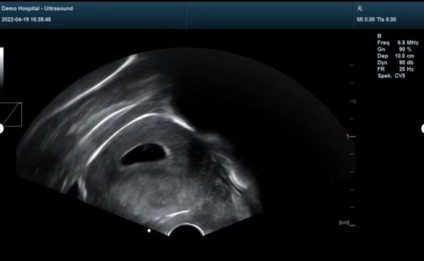

②全程超導(dǎo)可視:可視圖像顯影不受血污影響,操作方便,無(wú)菌安全,定位準(zhǔn)確,避免術(shù)中探測(cè)不到位、子宮穿孔、術(shù)后殘留等,是安全,精準(zhǔn),便捷的保障。